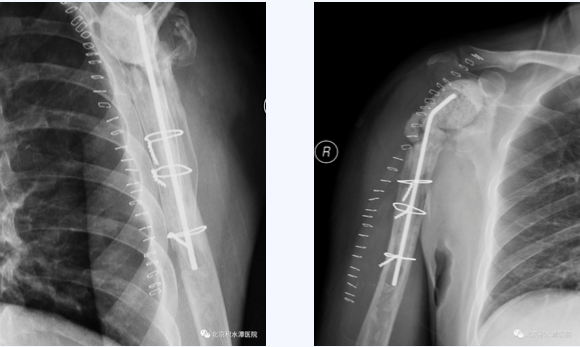

首先行假体取出、扩创控制感染,后期再行反肩关节置换。完善相关检查后,于2018年5月手术,扩创取出原假体,抗生素骨水泥植入。术中最大的难点在于肱骨侧假体、骨水泥及髓腔塞取出困难,而任何残留都可能会造成感染复发,术中采用肱骨干纵行劈开方式将假体、骨水泥和髓腔塞全部取出,并用钢丝捆扎修复,而肩胛盂侧的假体取出则较为顺利,但患者大小结节均已移位,肩袖组织完全挛缩。术后培养为表皮葡萄球菌,通过抗生素治疗,患者的感染顺利控制。